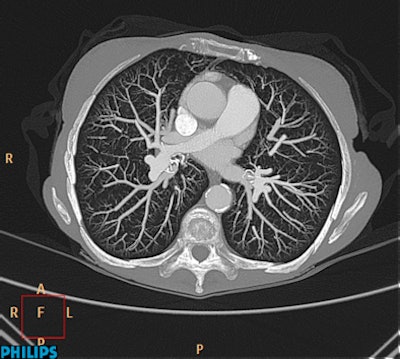

| Ingenuity CT with iDose demonstrates good contrast resolution and visualization of small vascular structures out to the peripheral lung. Image acquired in 6 seconds and reconstructed in 39 seconds. Other scan parameters: 80 kVp, 0.9 mSv, 138 mAs, 32-cm scan length. (Provided by Philips) |

Philips is also emphasizing dose reduction and cost-effectiveness in its new technologies displayed in the commercial exhibition. It is showing a new, faster version of its iDose iterative reconstruction technology on its recently introduced Ingenuity family of scanners.

"The addition of the Ingenuity Core and Ingenuity Core128 brings in-room upgradability, allowing customers to get the most value out of their investment and be poised for future growth," says Jamie Valliant, Philips CT product marketing manager. "And now with iDose, customers will not only benefit from improved spatial resolution, advanced clinical capabilities, and improved image quality at low dose, but also will experience even faster reconstruction speeds than before, allowing for quicker results and enhanced productivity and workflow."

Furthermore, iDose is now an option with the Brilliance CT Big Bore. This enables existing CT Big Bore customers to enjoy improvements in image quality at low dose, in addition to the tools available on the scanner today. Philips believes that iDose may offer unique capabilities for radiation oncology to help users reduce radiation exposure during the CT simulation process, while maintaining high image quality, which is important for contouring target volumes and critical structures in radiation therapy planning. The first deliveries of the systems are expected in the second half of 2012.